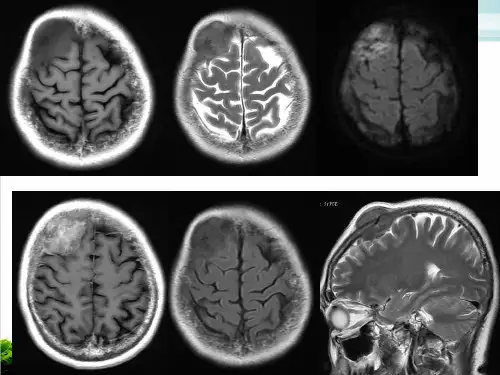

结果颅内原发淋巴瘤 T1WI 多呈稍低信号,T2WI呈等或稍高信号,FLAIR呈稍高或高信号,DWI多为稍高或高信号。

Gd-DTPA增强扫描病灶多呈明显强化。

病灶形态可为多发结节状、团块状或不规则形,侵及胼胝体时可呈“蝴蝶征”。

14例中MRI正确诊断5例,误诊9例,误诊主要原因是颅内淋巴瘤发生部位的不确定性及MRI表现的多样性。

结论 MRI能较好地分析颅内淋巴瘤的形态学改变及信号特点,可跟踪分析病情变化过程,但误诊率高,需进一步提高此疾病的诊断准确率。

M R 表现与脑灰质相比,多数病灶T1W I 为略低信号(7例),少数为等信号(2例),T2W I 多为等、略高信号(8例),少数为略低信号(1例)。

病灶边缘较清晰,均有占位效应,灶周水肿相对较轻。

注射G d-D TPA 后,8例病灶明显团块状强化,1例中央可见坏死无强化区,周边部呈不均匀强化。

影像学表现部位:深部灰质和白质;脑表面亦可见密度和信号:肿块在 CT 上呈高密度;T1WI 呈低/等信号,T2WI 呈高/等信号边缘:边缘锐利,呈圆形或椭圆形水肿:轻至中度脑室炎:病变易累及室管膜、脑膜囊变:极罕见出血:极罕见钙化:少见强化:明显均匀强化多发:常见case1:男,47 岁胼胝体膝部占位,T1WI,T2WI 呈等高信号,信号尚均匀 DWI 高信号,ADC 值减低;增强可见明显均匀强化,冠状位示「蝴蝶征」,矢状位见「尖角征」,边界清晰;周围见斑片状水肿。